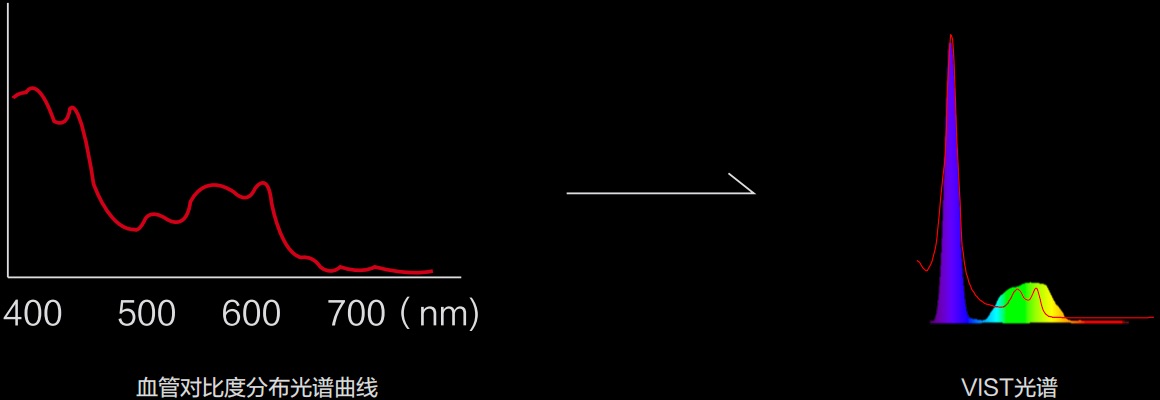

(Versatile Intelligent Staining Technology)

能够凸显黏膜浅层血管轮廓和黏膜表面微结构,适用于中、近景观察下的早癌精确诊断。